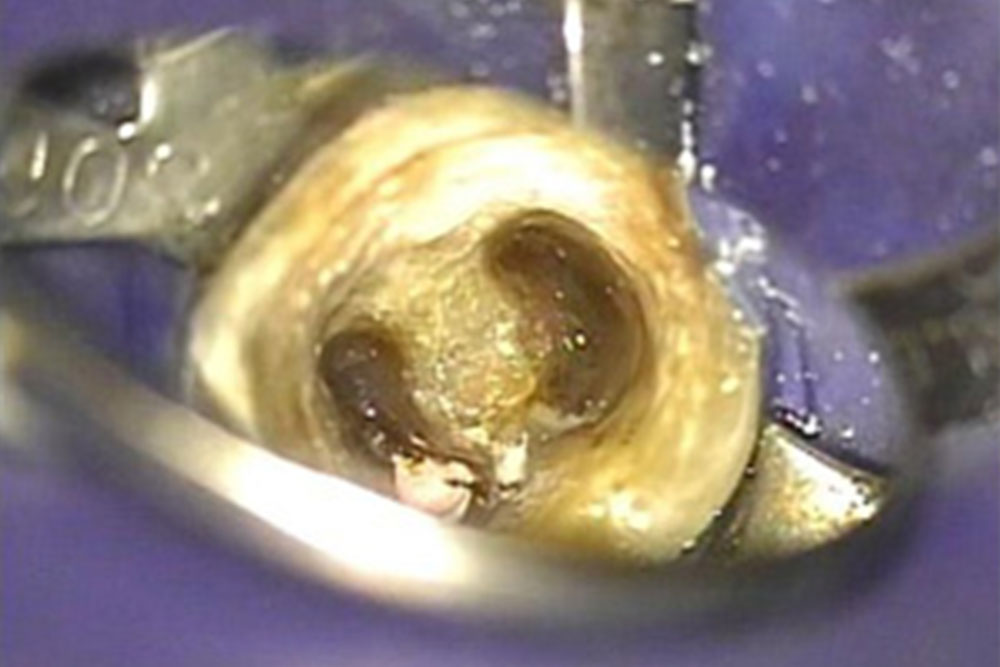

マイクロスコープで根管内を可視化

根管部は小さくて、暗いため肉眼では、感染物質の除去がしっかり行われているか、見落とした根管がないかなど、目での確認がしっかり行えず、勘や手探りといった精度の低い処置となってしまいます。

根管部は小さくて、暗いため肉眼では、感染物質の除去がしっかり行われているか、見落とした根管がないかなど、目での確認がしっかり行えず、勘や手探りといった精度の低い処置となってしまいます。

そのため当院では、肉眼の約30倍に視野を拡大できるマイクロスコープを使用して、視界が悪い根管内部を可視化することで精度の高い処置を可能にしています。

マイクロスコープの視野を体験

マイクロスコープは、肉眼の30倍の拡大視野で治療ができ、また目線と光軸がほぼ同軸なため細かい根の先端まで光が届いて見ることができます。歯を細部まで確認できるためしっかりした診断が可能になります。よく虫歯のチェック等で用いるペン型のモニターとは違います。モニターは写真なので、確認をしてもらうこと以外、治療上何の向上もありません。当院では、歯の内部に穴があいて通常必ず抜歯をしなくてはならない場合でも条件がそろえば特別な材料を用いてその歯を保存することが可能です。

肉眼の約10倍拡大図下での治療図

肉眼の約20倍拡大図下での治療図

肉眼の約30倍拡大図下での治療図